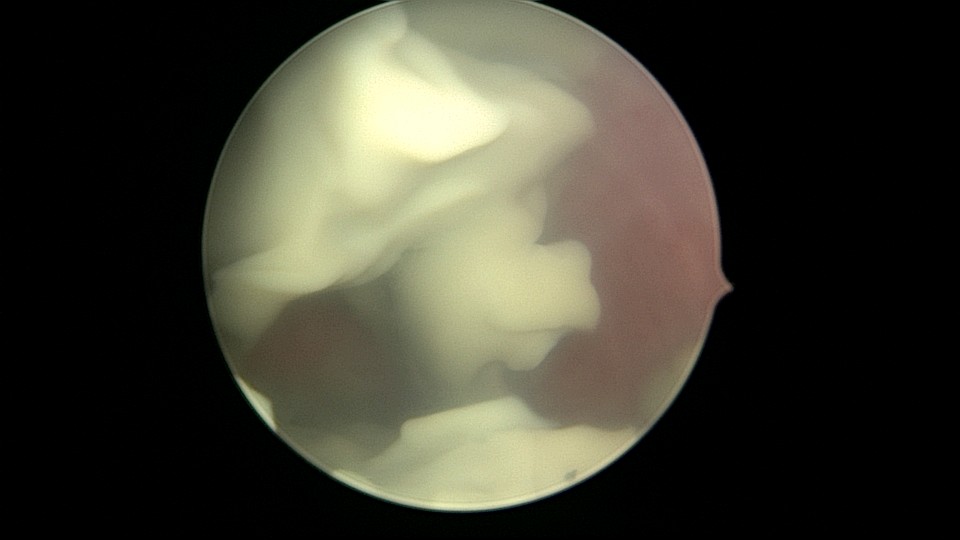

患者56岁,G3P1,顺产1次。安环20+年,绝经10年,下腹坠胀不适1周,B超提示子宫后位,宫内无回声区2.4cm×1.5cm。宫颈外口见节育环尾丝,环纵臂卡在宫颈管内,宫腔镜难以进入宫腔,取环后看到宫腔粘稠白色脓液,宫腔左侧前后壁粘连,膨宫液冲洗脓液,宫腔无其他异常。